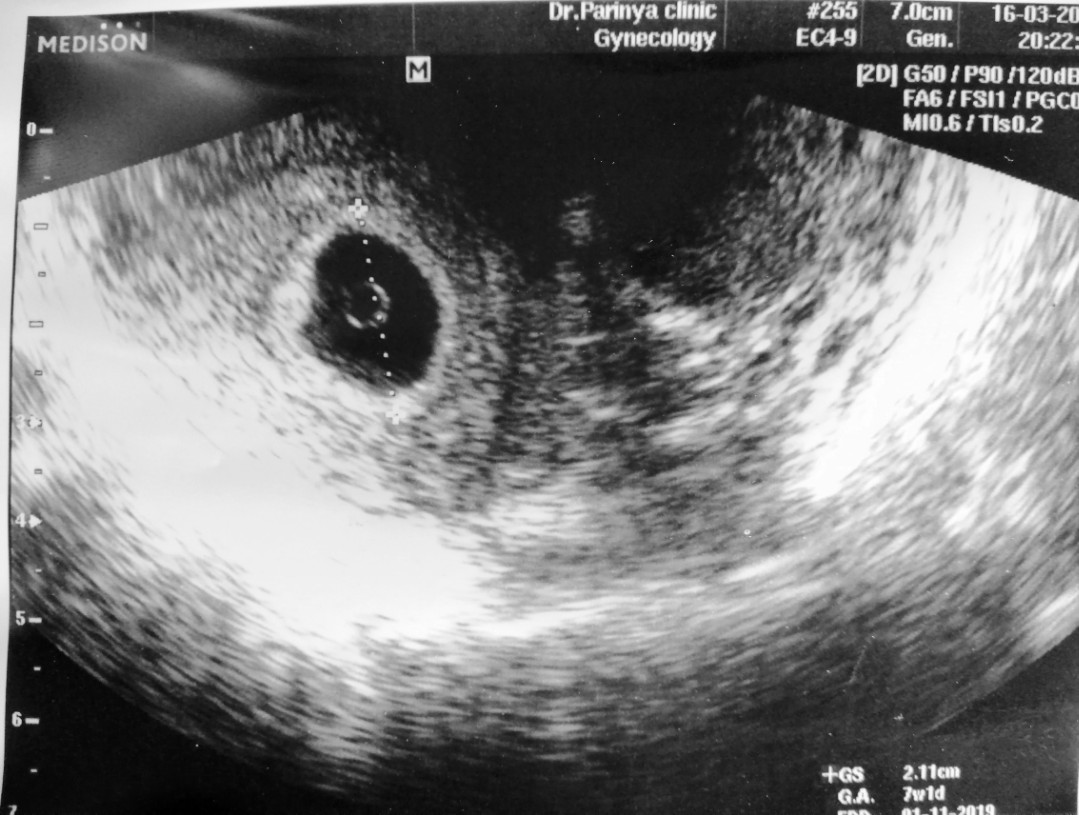

อันนี้ซาวผ่านช่องคลอดค่ะตอน8วีคแต่ยังไม่พบน้องเช่นกันค่ะ